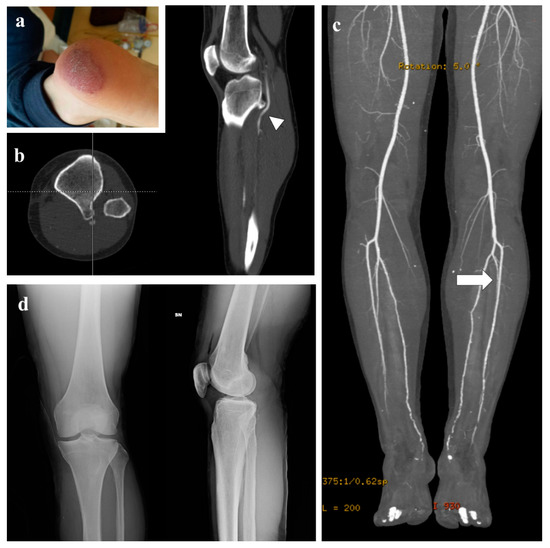

3. Representative Explanatory Case

| Present case | 1 | AI | Tibia | Thrombolytic Therapy | 34 | Solitary |